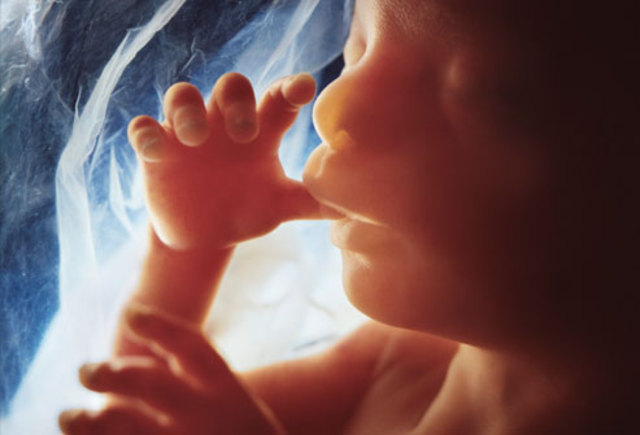

• Sense of Touch

Sense of Touch

The sense of touch has been developing, however the baby never really is alert about touching anything until about month five. It will explore the mom's uterus, the umbilical chord, and stroking its face.

• Baby's Last Major Reflex

Baby's Last Major Reflex

Baby starts sucking its thumb around this time.